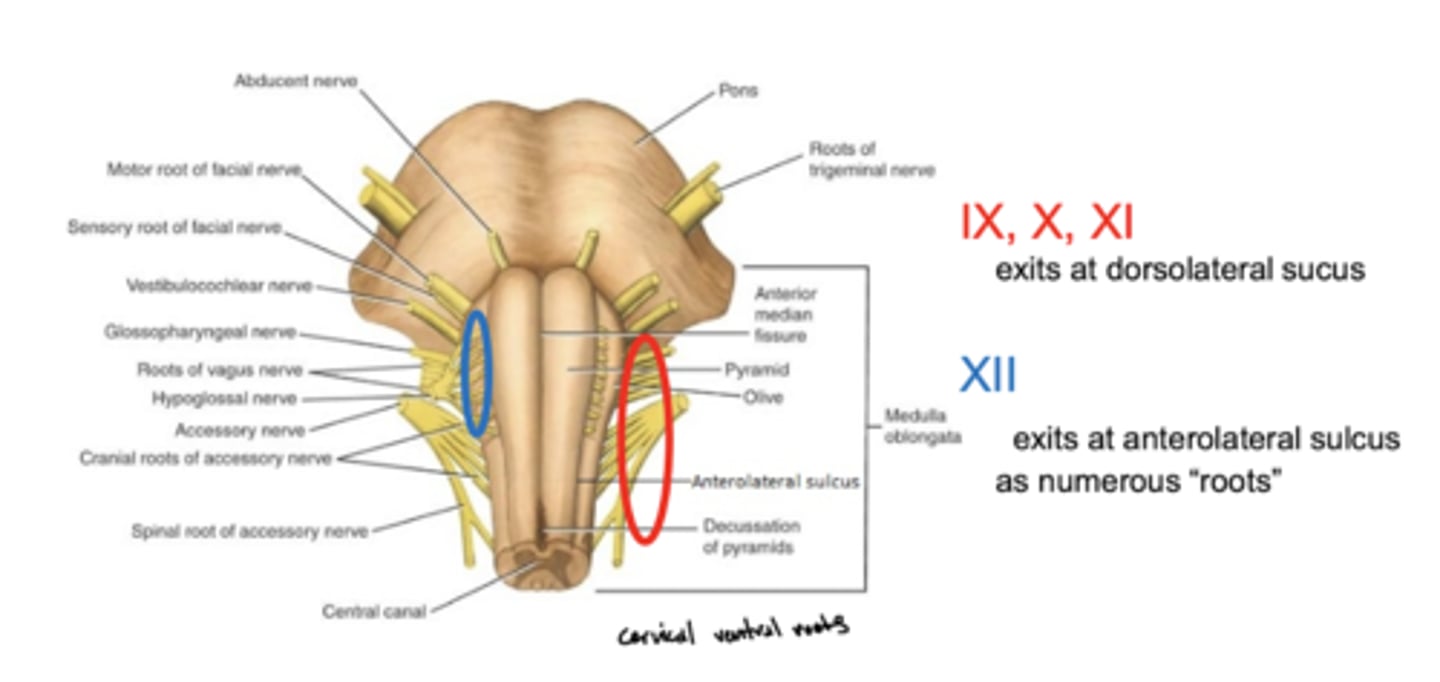

What cranial nerves reside in the medulla?

1. CN IX

2. CN X

3. CN XI

4. CN XII

Where do CN IX, X, and XI exit the medulla oblongata?

exit the dorsolateral sulcus (

posterolateral sulcus)

3rd sulcus (counting medial to lateral) -- most lateral

Where does CN XII exit the medulla oblongata?

anterolateral sulcus -- as numerous roots

2nd sulcus (counting medial to lateral)